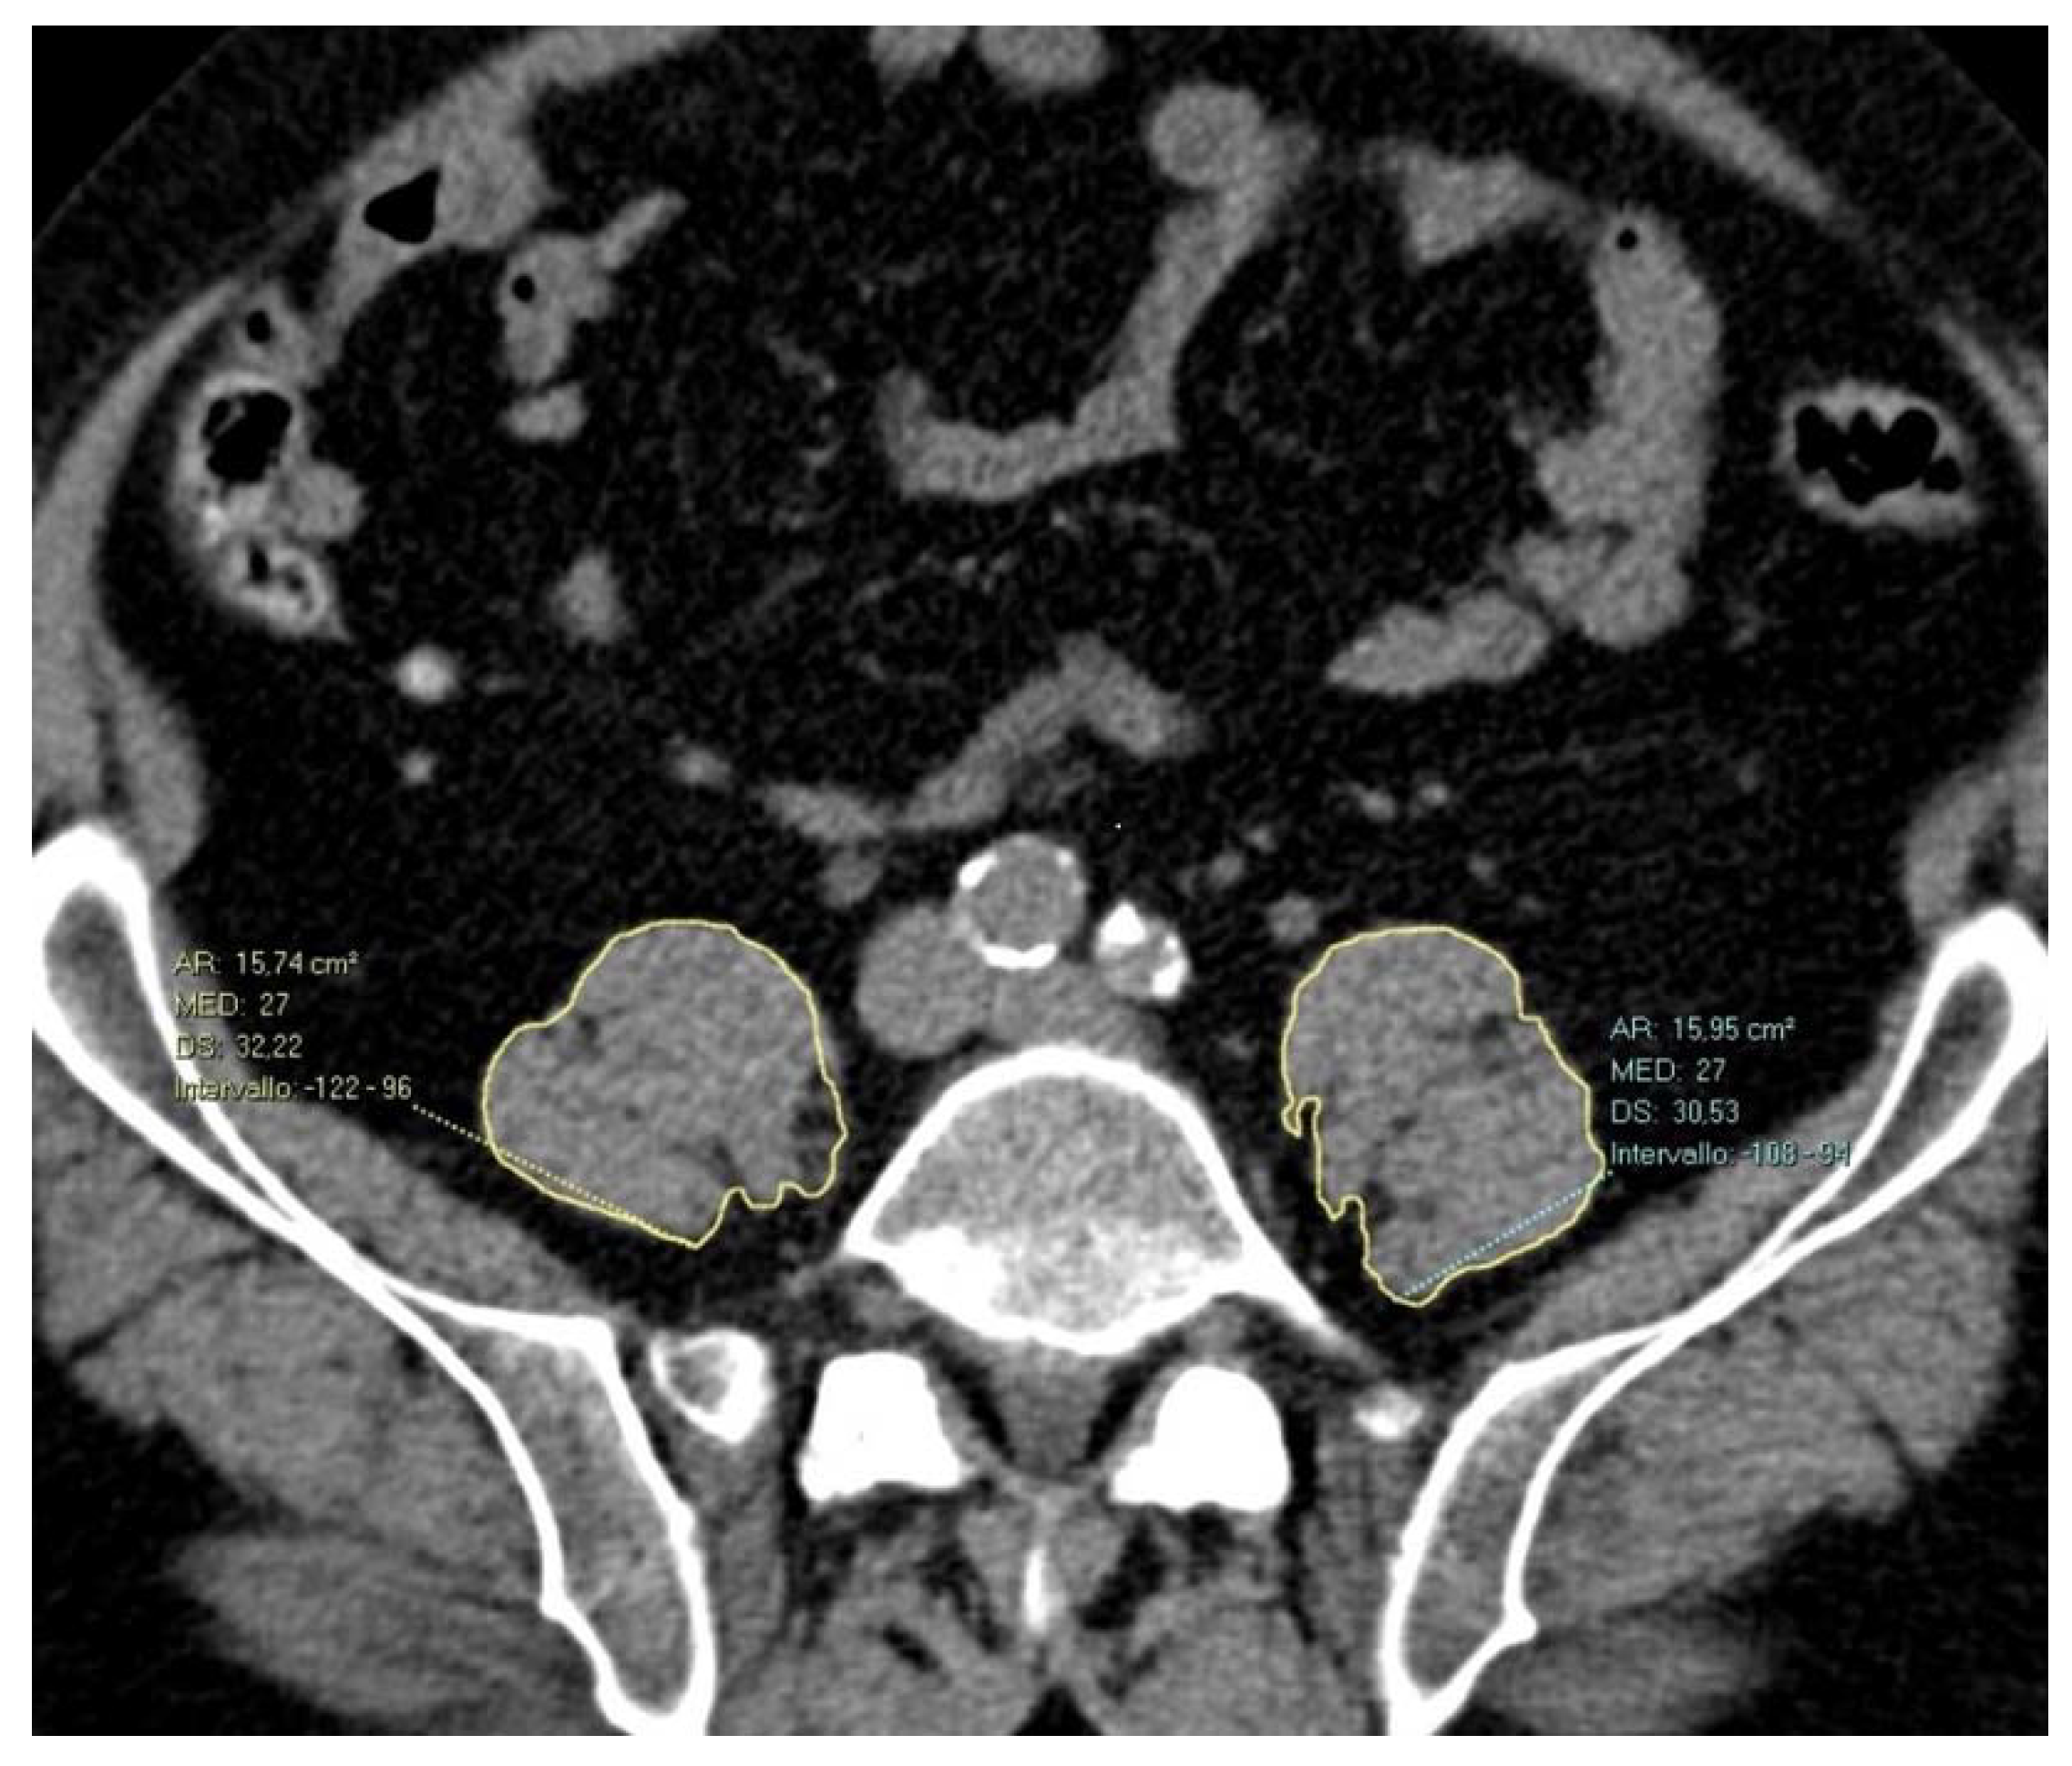

Psoas Cross-Sectional Measurements Using Manual CT Segmentation before and after Endovascular Aortic Repair (EVAR)

2.2. Image Acquisition and Post-Processing